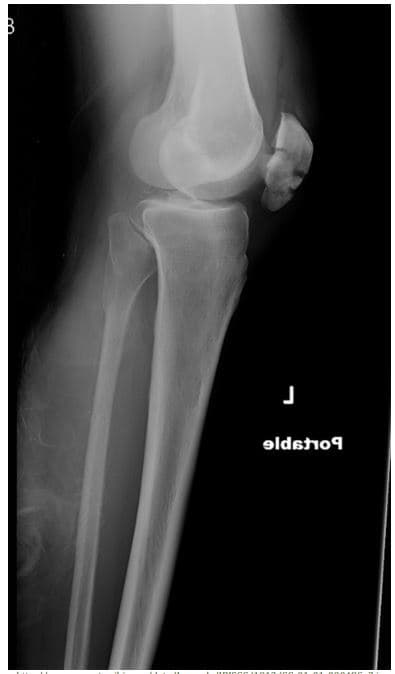

How would you describe the fracture?

Name the type of fracture

List ALL the bones present

What may have caused the abnormality?

Are these bones axial, appendicular, or both?